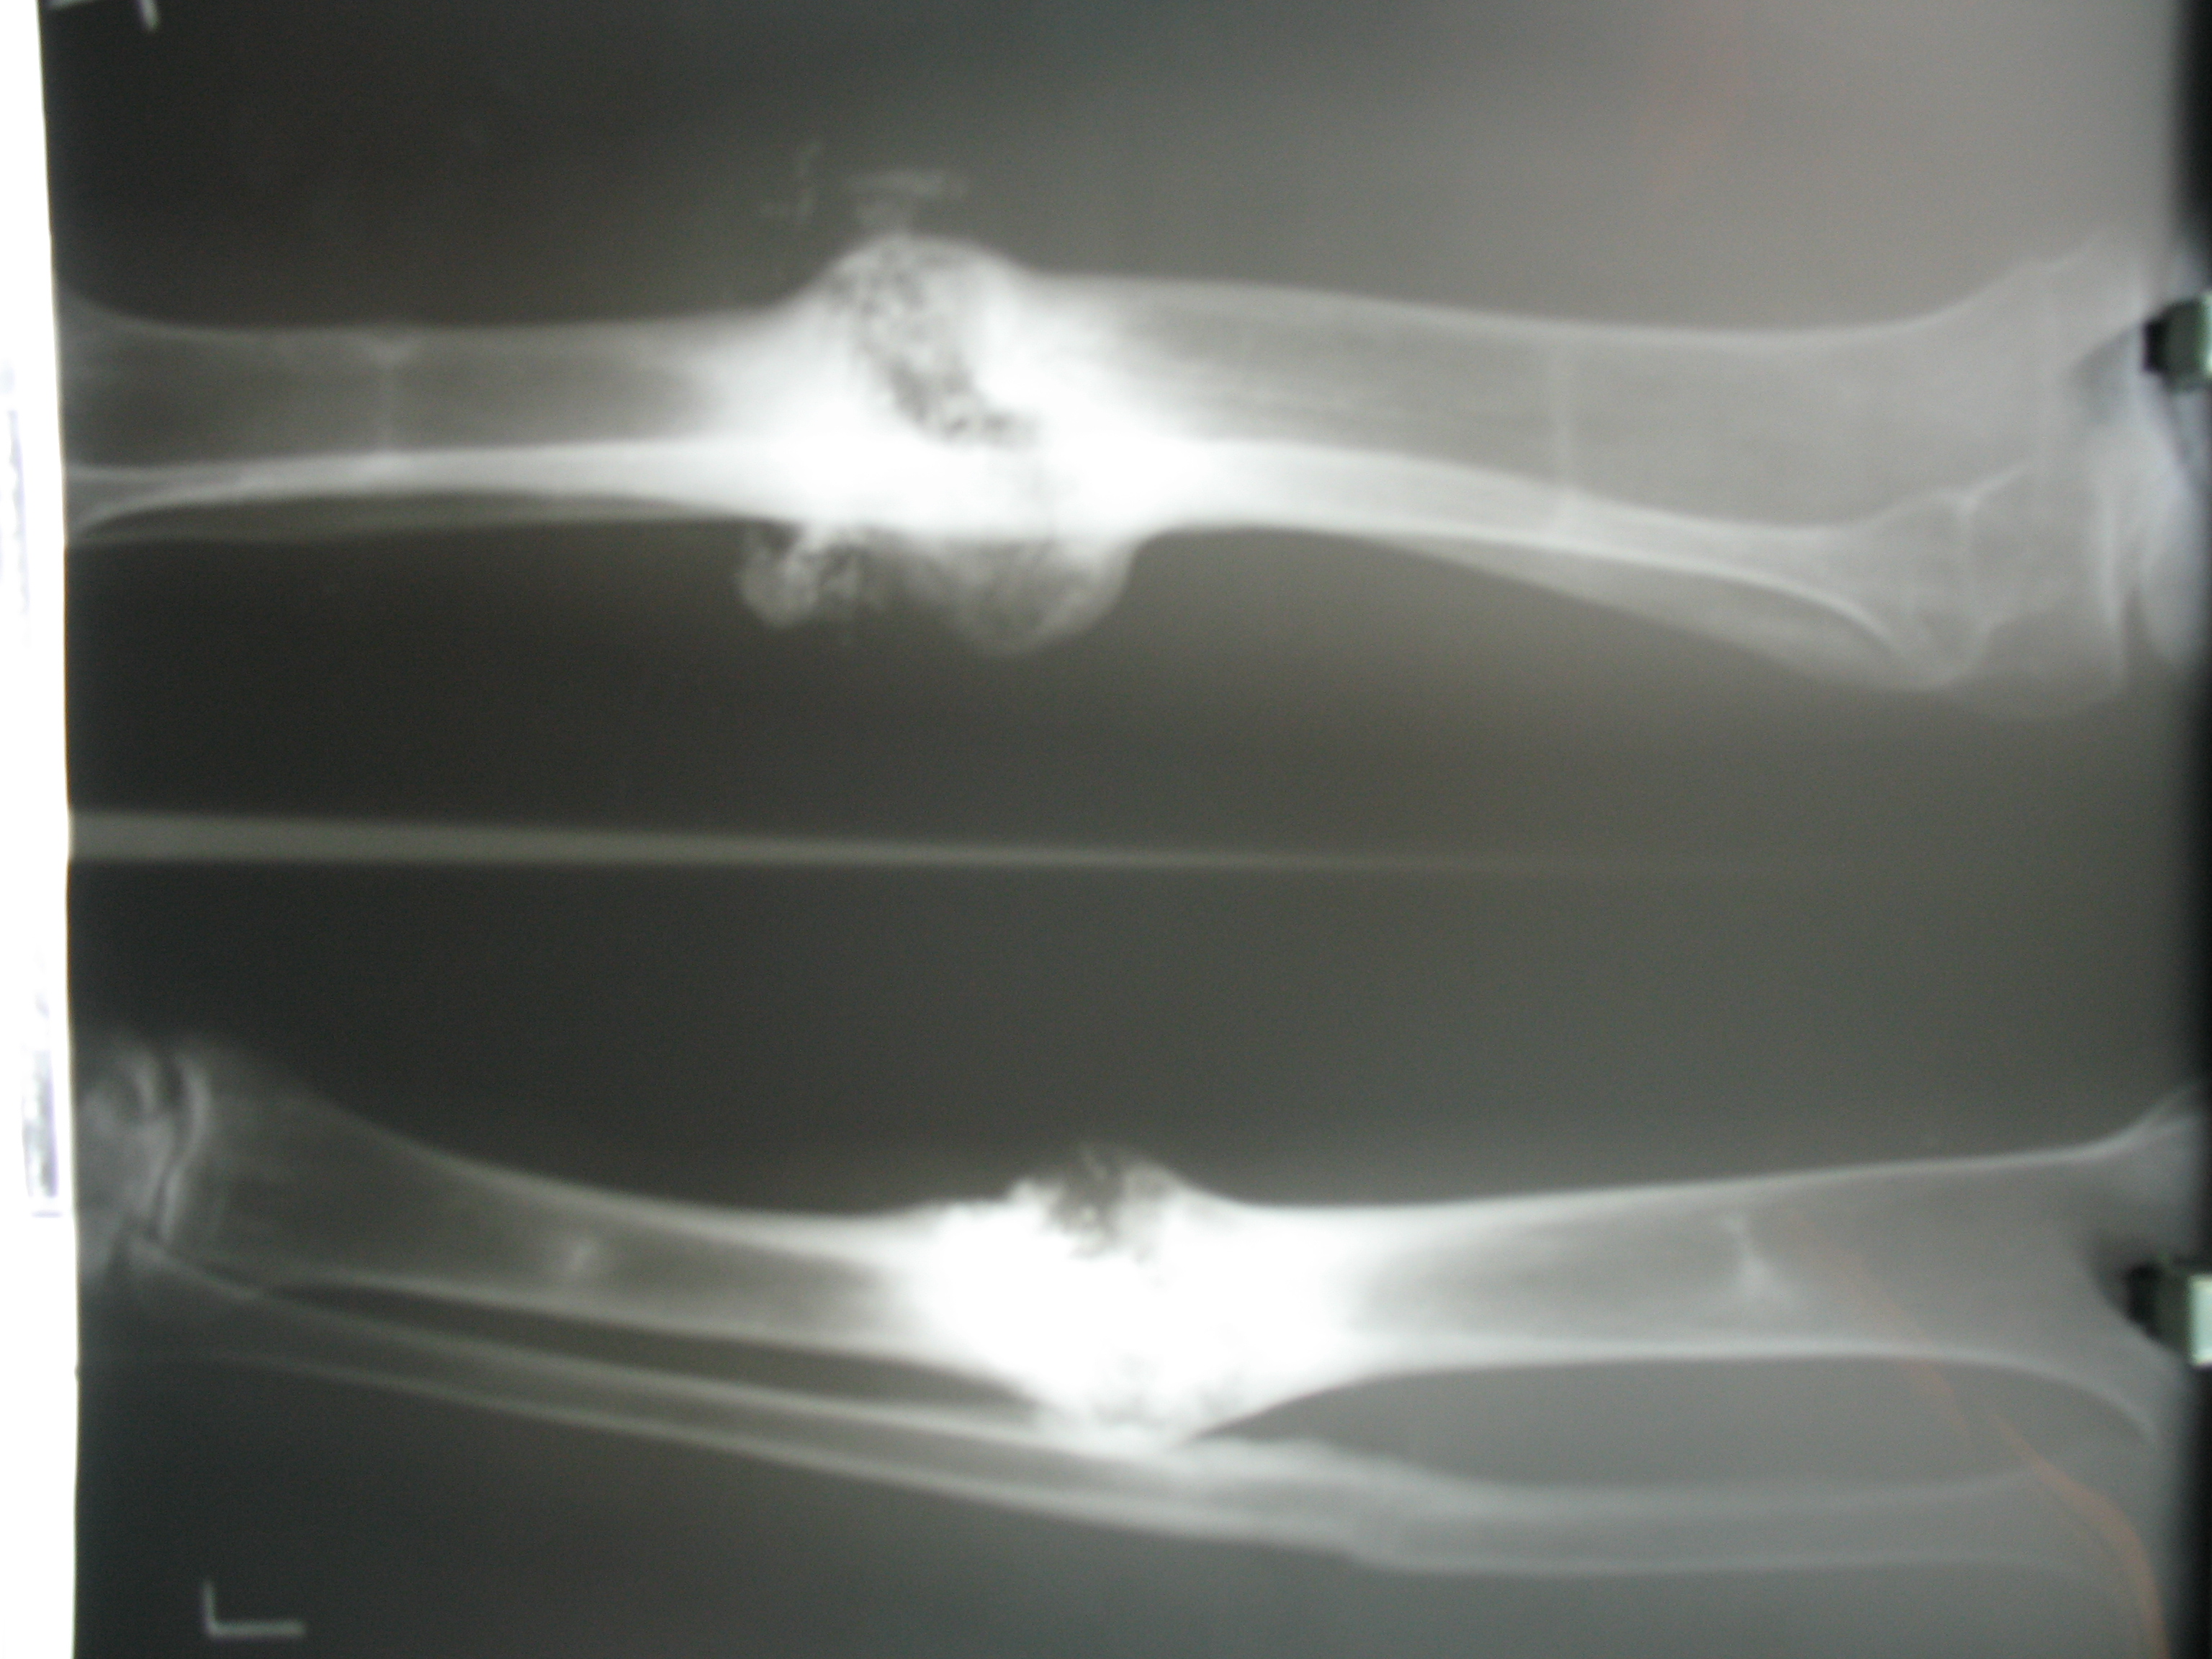

تهیه و تامین تجهیزات ارتوپدی و مشارکت در انجام اعمال جراحی ارتوپدی و عمل‌های نادر عضو تیم جراحی افزایش قد -جهت ترمیم شکستگی های قدیمی و جوش نخورده گی ها -طویل کردن اندامها- طویل کردن انگشت قطع شده - تعویض مفصل لگن _تعویض مفصل زانو _ بازسازی رباطACLوPCL_اصلاح ناهنجاریهای مادر زادی -با همکاری پزشکان و متخصصان مجرب آموزش دیده در روسیه و اتریش و سوئیس بروش جراحی ایلیزاروف و lon و lsa و واگنر و اسلایدینگ نیز جدید ترین روش افزایش قد و اندام در سال 1397 بنام hil هیل برای اولین بار- افزایش قد به 6 روش جراحی و جدیدترین روش در اروپا و روسیه. آدرس مطب _تهرانسر بلوار اصلی مجتمع سهند طبقه4 واحد 410

مبنای تئوری: استرس تنش و دیستراکشن استئوژنزیس(استخوان سازی بین دو سطح استخوانی زنده و پر عرق)

روش دیستراکشن استئوژنزیس: تاخیر: 5 روز       ریت: 1 میلی لیتر             ریتم:25%(4 مرحله در روز)

ایندکس ترمیمی: تعداد ماه از زمان عمل جراحی تا تشکیل استخوان با قابلیت تحمل وزن بدون لوازم کمکی اتفاقات در زمان دیستراکشن اتئوژنزیس بعد از کورتیکوتومی:

1. تشکیل هماتوم حاوی فیبرین (هفته اول: تشکیل فیبرو بلاستهای دوکی در میان باندلهای موازی کلاژن)

2. تشکیل پل فیبرو واسکولار(قابل تغذیه بودن فیبرین حاصله)توسط سلولهای فرانشیمال حاوی کلاژن یعنی در طی

هفته اول از شروع دیستراکشن یک بافت فیبری آواسکولار ناحیه گپ را پل می زند .

(پل فیبرو واسکولار)و شروع رسوب کلاژن    f123-در طی هفته دوم:ظهور سلولهای استئو بلاست در دوطرف

و استوئید .در آخر هفته دوم: مینرالیزاسیون  اولیه همانند استالاگمیت و استا لاگتیت از دو سطح کورتیکوتومی به گسترش می یابد(مثل ستون)f12مرکز